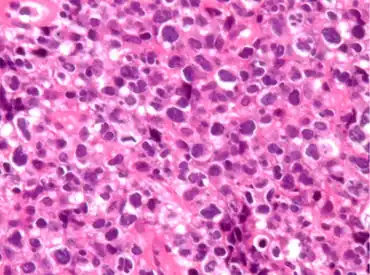

| Pathological features observed during staining. | |

PMLBCL is CD20 positive, expresses pan-B markers including CD79a, and has clonal immunoglobulin gene rearrangements and mRNA but paradoxically does not express cytoplasmic or cell surface immunoglobulin.[2]: 370